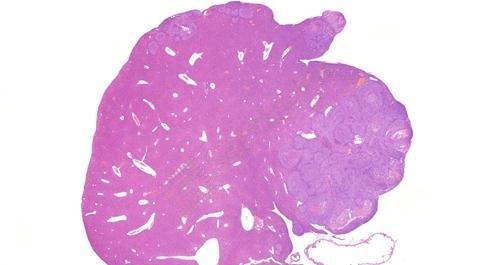

3、肝转移瘤HE染色